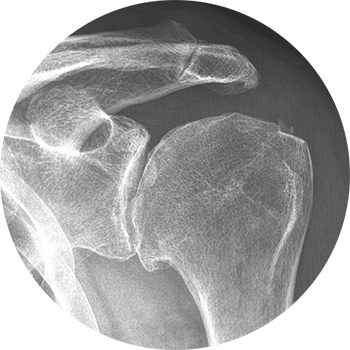

Das AC-Gelenk verbindet das äußere Ende des Schlüsselbeins (Clavicula) mit dem Schulterdach (Acromion) und ist ein integraler Bestandteil des Schultergelenkkomplexes. Es ermöglicht nur geringe Rotationsbewegungen, vor allem bei Armbewegungen über Kopf. Aufgrund seiner starken Bandführung ist das Gelenk kaum aktiv trainierbar.

Beschwerden im AC-Gelenk entstehen in der Regel durch:

Direkte Gewalteinwirkung, etwa bei Stürzen im Sport – was zu einer sogenannten ACG-Sprengung führen kann

Verschleißbedingte Veränderungen (Arthrose), insbesondere im mittleren und höheren Lebensalter

Eine akute Verletzung des Schultereckgelenks – insbesondere bei Bandverletzungen oder -rissen – äußert sich durch plötzliche, starke Schmerzen und eine sichtbare Hochstellung des Schlüsselbeins. Bewegungen im Schultergelenk sind oft nur unter Schmerzen möglich.

Im Verlauf kann es auch bei konservativ versorgten oder operierten Fällen zu späteren Arthrosebeschwerden kommen. Diese werden meist als dumpf, tiefsitzend empfunden und können in den Nacken oder die Halsregion ausstrahlen.

Die Diagnose wird in der akuten Phase häufig schon durch das klinische Erscheinungsbild und die körperliche Untersuchung gestellt. Eine deutlich hervortretende Schlüsselbeinspitze, verbunden mit lokalem Druckschmerz, gilt als typisches Zeichen. Bei chronischen Veränderungen äußern sich die Beschwerden meist durch belastungsabhängige Schmerzen, insbesondere bei Überkopfbewegungen oder bei längerem Liegen auf der betroffenen Seite.

In bestimmten Fällen kann ein diagnostischer Infiltrationstest Klarheit bringen: Hierbei wird das Gelenk gezielt betäubt, um festzustellen, ob die Beschwerden tatsächlich vom AC-Gelenk ausgehen.

Die Behandlung richtet sich nach dem Ausmaß der Bandverletzung. Leichtere Formen (z. B. Grad I–II) werden meist konservativ behandelt – mit Ruhigstellung, Schmerztherapie und späterer Physiotherapie.

Ab einem höhergradigen Bänderriss (Grad III oder höher) wird häufig eine operative Stabilisierung empfohlen. Hierbei stehen verschiedene Verfahren zur Verfügung (z. B. mit Implantaten wie Hakenplatten oder Fadensystemen), die alle vergleichbare Erfolgsraten zeigen. Wichtig ist, dass die Operation zeitnah erfolgt, um optimale Ergebnisse zu erzielen.

Besteht eine länger andauernde Instabilität, kann zu einem späteren Zeitpunkt eine aufwendigere Stabilisierungsoperation durchgeführt werden.